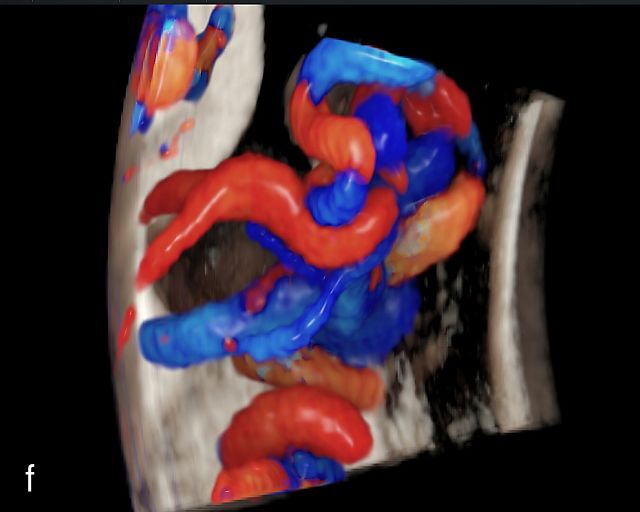

There are three types of vasa previa.30,262 In Type 1, the cord inserts into the membranes rather than the placenta. Unprotected vessels then traverse the membranes over the cervix to insert into the placenta (Figure 21a; Video 12). In Type 2, unprotected vessels running through the membranes over the cervix connect the main placental lobe with an accessory lobe (Figure 21b).263 In Type 3, there is generally a normal placental cord insertion, and unprotected vessels exit one placental edge, run through the membranes over the cervix and then boomerang to insert into the placental edge at another site (Figure 21c).25,28,29,264 Regardless of the type, all these expose the fetus to the same risks.

21